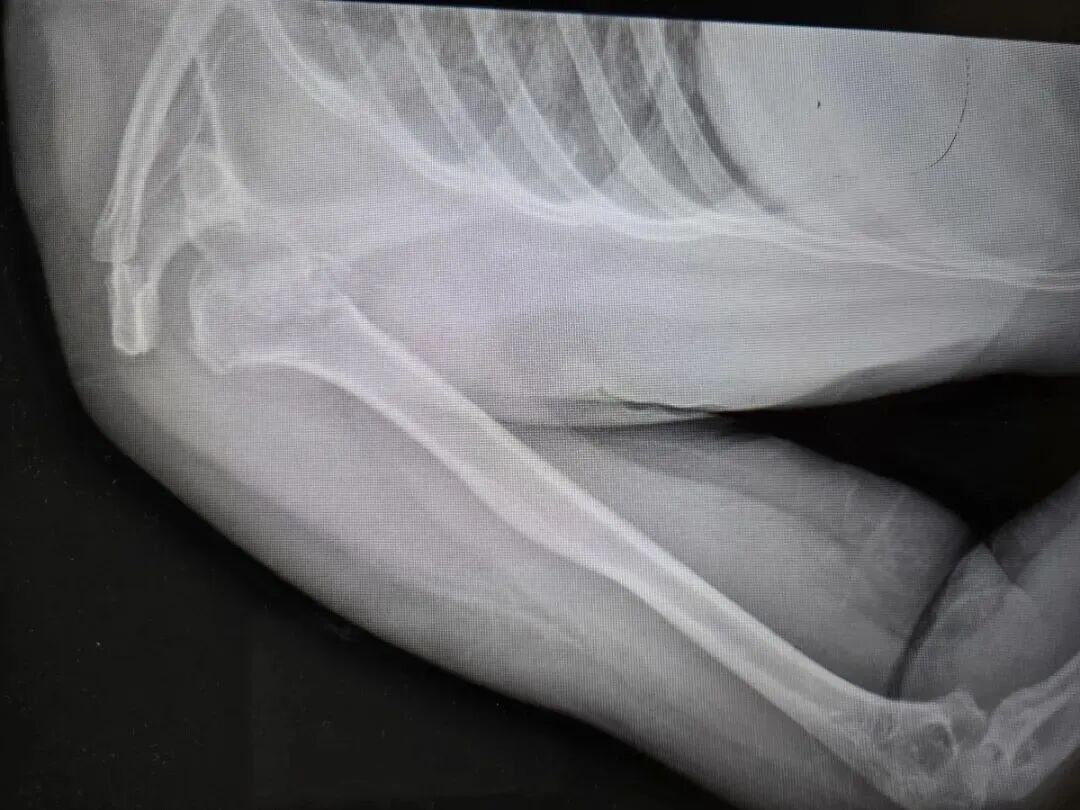

近日,河南50岁的张大姐在睡梦中突发肩膀粉碎性骨折,骨头碎裂成七八块,其丈夫表示,事发时张大姐全程均躺在床上,未受外部撞击。

患者被送往河南省人民医院后,该院创伤骨科主任刘涛坦言,初见病情时十分意外,这类严重骨折通常由高空坠落、车祸撞击等高能外力导致。随后,创伤骨科与神经内科联合会诊检查,最终查明病因是张大姐癫痫发作,上肢猛烈抽搐挥舞引发骨折。

刘涛表示,癫痫发作导致此类粉碎性骨折的情况,在临床诊疗及相关文献中均极为罕见。

针对张大姐的病情,医院诊疗小组制定了专属治疗方案,手术中不仅将劈裂的肱骨头、后脱位等四大部分共七八块碎裂骨头按原貌完整复位,还对受损肌腱进行了修复,并为骨骼塌陷部位填充支撑骨。